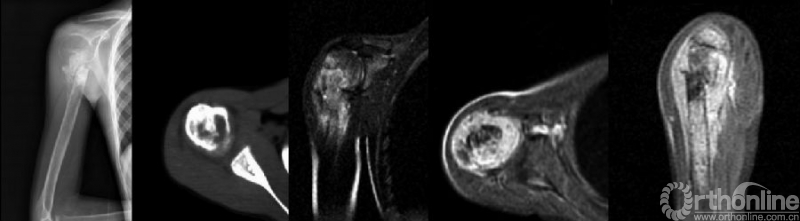

骨肉瘤是儿童和青少年最常见的原发恶性骨肿瘤,其预后差。目前骨肉瘤患者5年生存率约为60-70%,转移患者则更低。多种因素已被证实影响骨肉瘤患者预后。病理性骨折(pathologic fractures,PFs)是骨肉瘤患者常见并发症之一(图1),但PFs对骨肉瘤患者预后的影响以及针对该类患者治疗方式的选择一直以来存在争议。因此,有必要针对这一问题进行文献回顾和讨论。

图1. 右肱骨近端骨肉瘤的病理性骨折(来自Xie L,J Surg Oncol.2012.)

PFs在骨肉瘤患者中发生率约为5%-10%,尤其好发于高级别原发性骨肉瘤患者,肱骨和股骨多见(图2)。骨肉瘤患者发生PFs的原因包括:组织分化程度、细胞密度、骨皮质破坏、骨基质丢失、活检或化疗后肿瘤坏死致骨机械支撑强度减弱等。